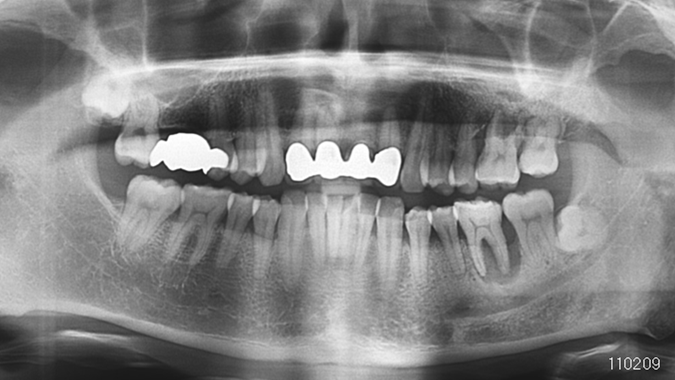

Clinical case: Bone growth in deepest thread of 8.0mm AnyRidge fixture

- Courtesy of Dr. Kwang Bum Park -

AnyRidge, KnifeThread, extraction socket, initial stability, allograft, osseointegration, Dr. Kwang Bum Park, mandibular posterior, single replacement, Mega-Oss

Implant system-AnyRidge, Regeneration-Mega-Oss

Clinical case: Bone filling into the bottom of deepest thread at 8.0mm AnyRidge fixture

AnyRidge, Knifethread ,extraction socket, ,initial stability ,Allograft, ,osseointegratio ,Dr. Kwang Bum Park, , Mandibular, Single replacement, AnyRidge, Mega-oss,